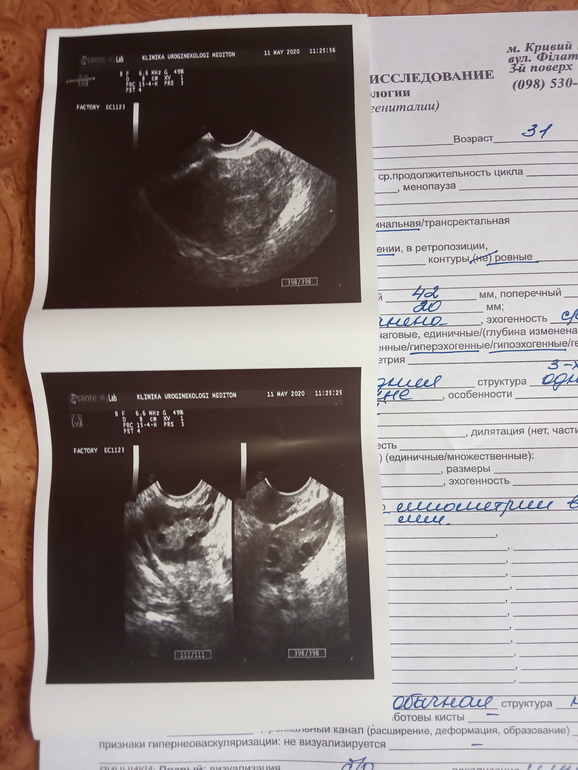

При поликистозе размер яичников огромный. Правый у вас нормальных размеров, а вот левый да соглашусь с врачом, огромный. Схож как при СПКЯ.

Я бы сдала на гормоны и мониторила фолликулы несколько раз за цикл.

Ну фоликов да, много. Но поликистоз ставят не только по узи, а в купе с анализами на гормоны (андрогены высокие, лг и ФСГ в неправильном соотношении), и узи не одно должно быть, а 2 в одном цикле, чтоб понять, что с фоликами произошло - доминантный рос или нет, лопнул или нет, перерос в кисту или нет.

Ну, все не так страшно, пока в заключении ставят МФЯ, в СПКЯ не уверенны. Нужно посмотреть есть ли О и сдать гормоны. С МФЯ можно самостоятельно забеременеть.

Я выбираю жить в кайф

Планируем ещё одного...Со вторым было ксерареао 5 лет назад,пол года назад ВБ,прошлый цикл первый планирующий,вот с него и начались проблемы....был очень длинный 48 д.,но овуляция была.На УЗИ аденомиозу значения не придали,сказала,что эндометрий хороший,матка в норме,вот только яичники....Левый увеличен и много фоликов.Сейчас он и беспокоит, потягивает,кроме этого симптомов нет...